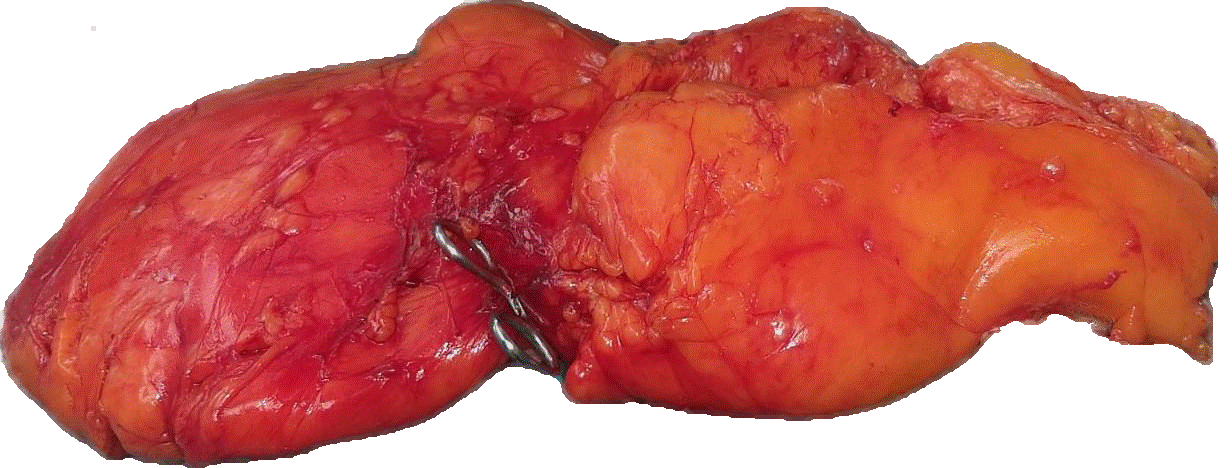

Con todos los estudios realizados la paciente es programada para intervención quirúrgica con diagnostico pre y postquirúrgico de lipoma mesentérico gigante donde se le realiza una laparotomía exploratoria más exéresis del lipoma mesentérico, mediante la realización de una incisión supra-infra umbilical media, reportando como hallazgo transquirúrgico:

Un tumor lipomatoso mesentérico gigante de aproximadamente 50x40 cm de diámetro con múltiples lóbulos, de origen en el mesenterio, sin compromiso de asas intestinales ni de estructuras adyacentes (figura 3).

Figura 3. Hallazgo transquirúrgico de lipoma mesentérico